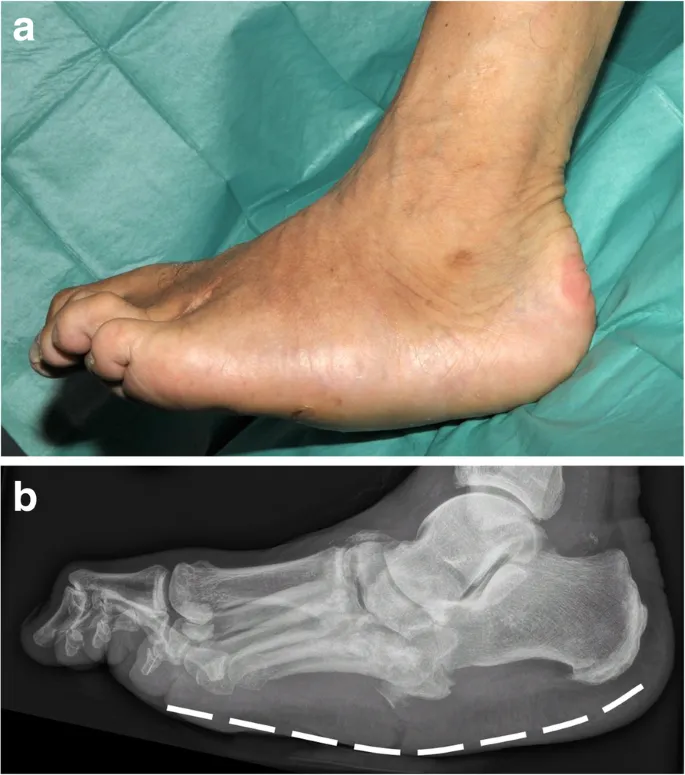

AAFD - Flat Foot Fixes

AAFD: Progressive flatfoot from Posterior Tibial Tendon Dysfunction (PTTD).

Charcot Foot - Stability Strategies

- Patho: Neurotraumatic (insensate microtrauma) & Neurovascular (↑ flow → osteolysis).

- Risk: DM + peripheral neuropathy.

- Eichenholtz Stages (X-ray):

- 0 (Prodromal): Inflammation, normal X-ray.

- I (Development): Fragmentation, dislocation, debris.

- II (Coalescence): Debris absorption, early fusion.

- III (Reconstruction): Remodeling, deformity (rocker-bottom).

- Clinical: Acute (hot, red, swollen, bounding pulses) vs. Chronic (deformity, instability).

- Goal: Stable, plantigrade, shoeable foot.